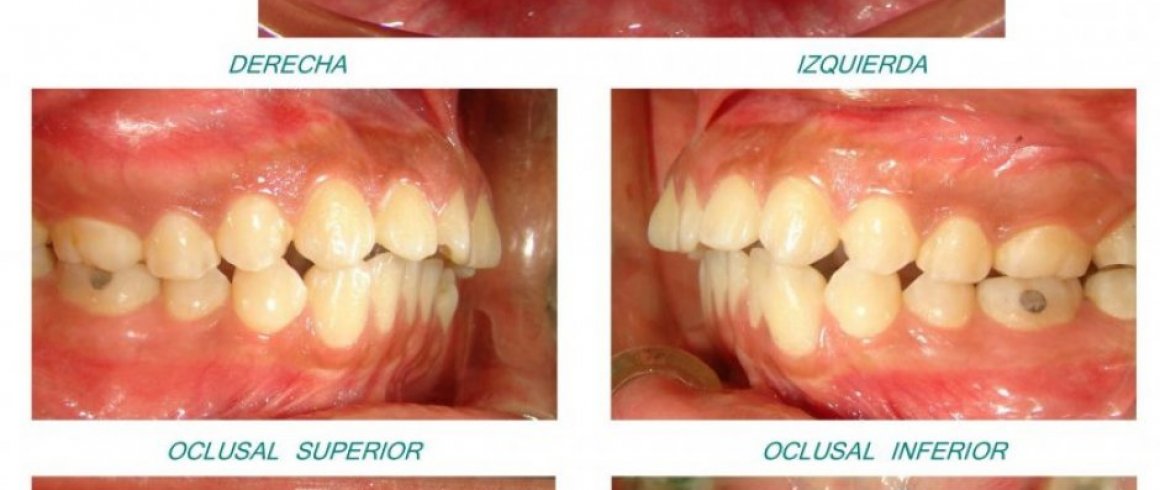

- Fotografía Digital

- Fotografías Intraorales